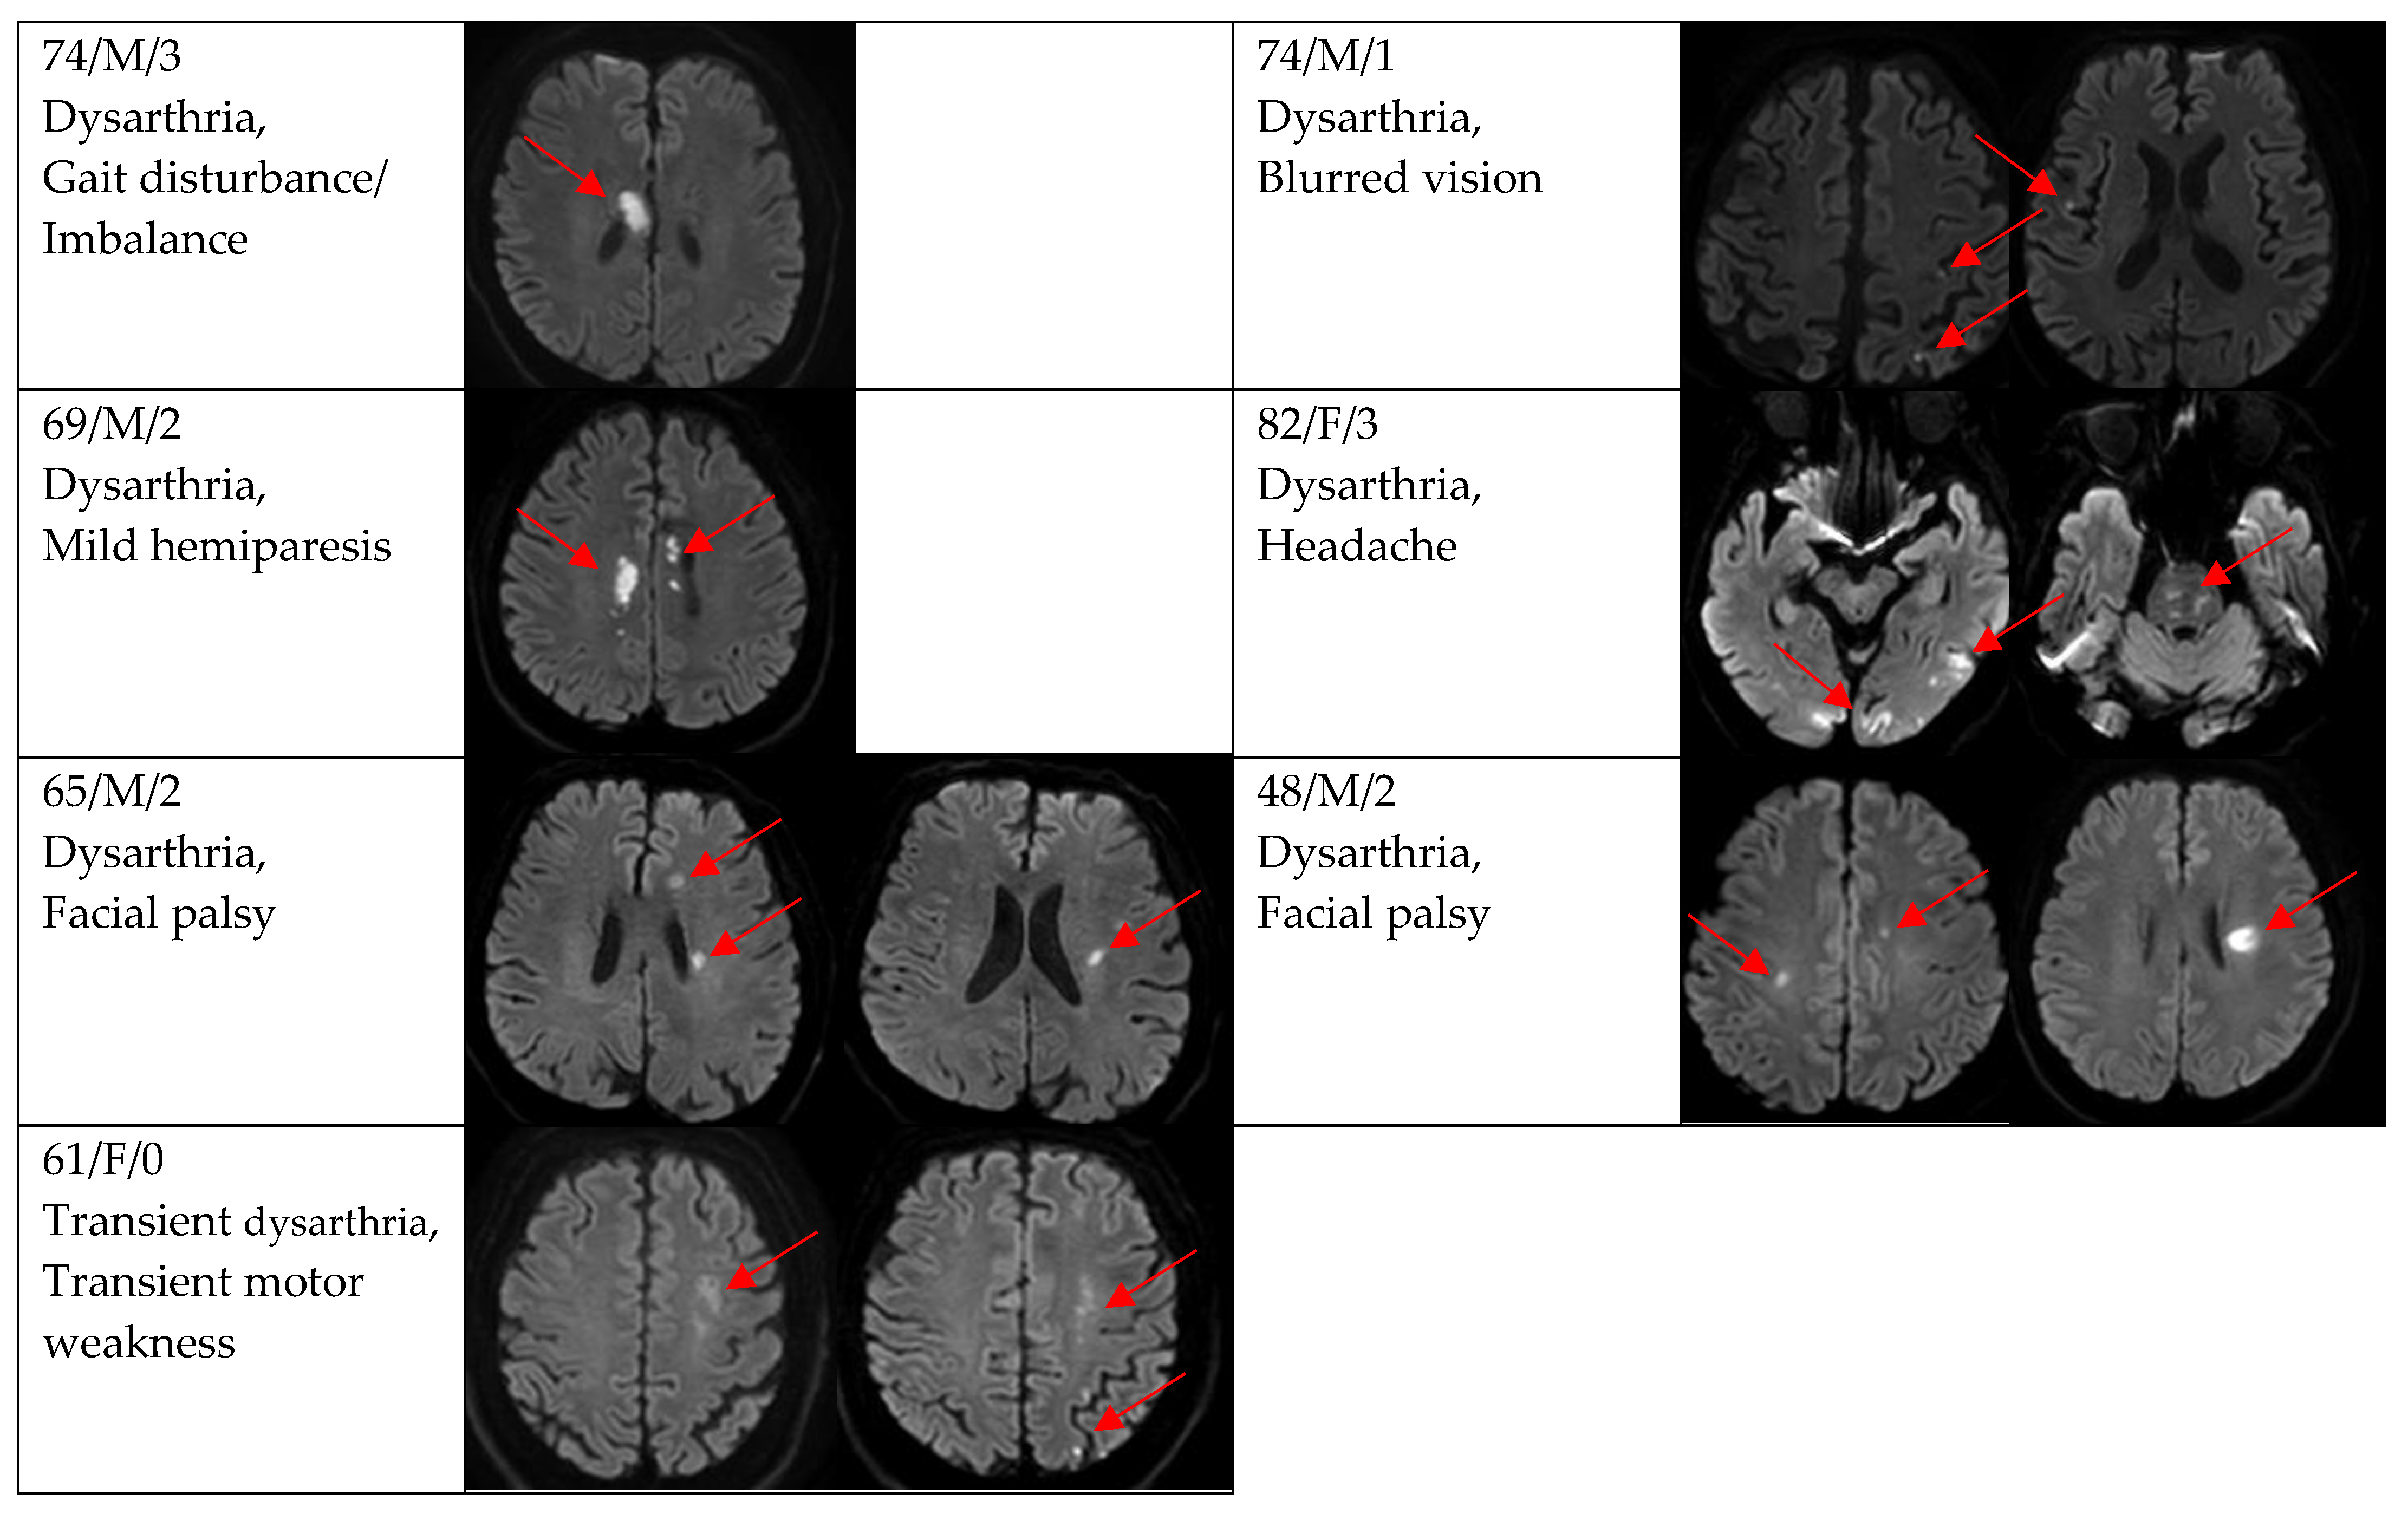

| Gait disturbance/imbalance | 9 (19.2) | 1 (7.7) | 8 (23.5) |

| Facial palsy | 8 (17.0) | 1 (7.7) | 7 (20.6) |

| Mild hemiparesis | 5 (10.6) | 2 (15.4) | 3 (8.8) |

| Limb ataxia | 3 (6.4) | 0 (0.0) | 3 (8.8) |

| Transient motor weakness | 3 (6.4) | 0 (0.0) | 3 (8.8) |

| Headache | 1 (2.1) | 0 (0.0) | 1 (2.9) |

| Blurred vision | 1 (2.1) | 0 (0.0) | 1 (2.9) |

| DWI positivity | 12 (66.7) | 29 (87.9) | 0.154 |

| Single and small lesion | 10 (83.3) | 16 (55.2) | |

| Multiple or territorial lesions | 2 (16.7) | 13 (44.8) | |

| 2 | 0 (0.0) | 14 (48.3) | |

| 3 | 0 (0.0) | 5 (17.2) | |

| 4 | 0 (0.0) | 3 (10.3) | |